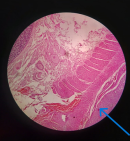

Follow-up and outcomes: postoperative recovery was uneventful, and the patient was discharged on postoperative day five. Histopathology showed clear cell renal cell carcinoma (Figure 4) with direct serosal invasion of the colon (Figure 5) and positive lymph nodes for metastasis (pT4N1), ISUP grade 4, with sarcomatoid (Figure 6) and rhabdoid differentiation (Figure 7). The patient is currently attending the surgical outpatient clinic with plans for targeted therapy.

Figure 5: section of the colon showing point of invasion of the serosal (H&E 40X)